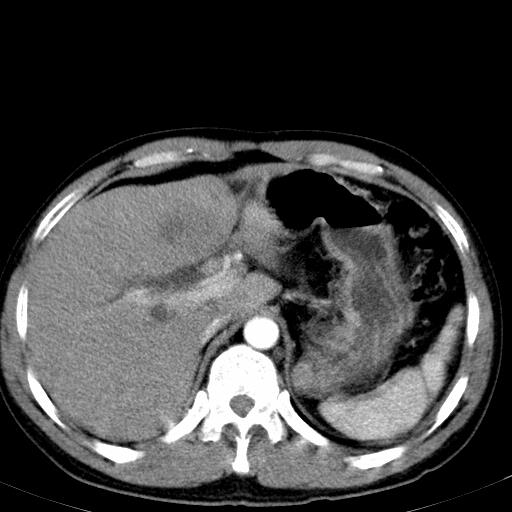

患者上腹部疼痛一月余,伴巩膜黄染;

实事求是的说,强化效果很一般,重点部位应重点观察,但有一点可以明确:肝门部胆管细胞癌。

考虑肝左叶胆管细胞癌侵犯肝门区并肝内胆管及肝总管扩张。

肝左叶肿块清度增强,所在的叶胆管扩张。考虑胆管细胞癌。